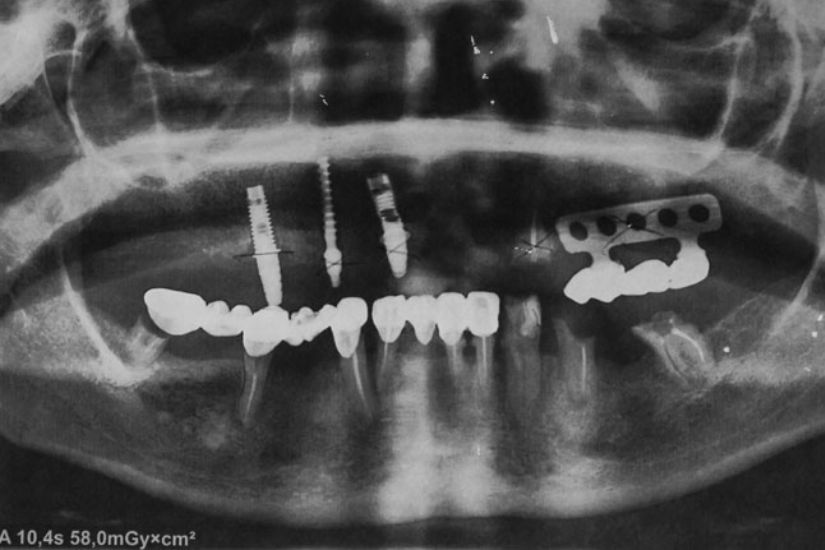

Dental Rehabilitation Using Alpha Dent Implant in Case of Reconstructed Mandible after Excision of Ossifying Fibroma

Dental Rehabilitation Using Alpha Dent Implant in Case of Reconstructed Mandible after Excision of Ossifying Fibroma Dr. Parit Ladani MDS